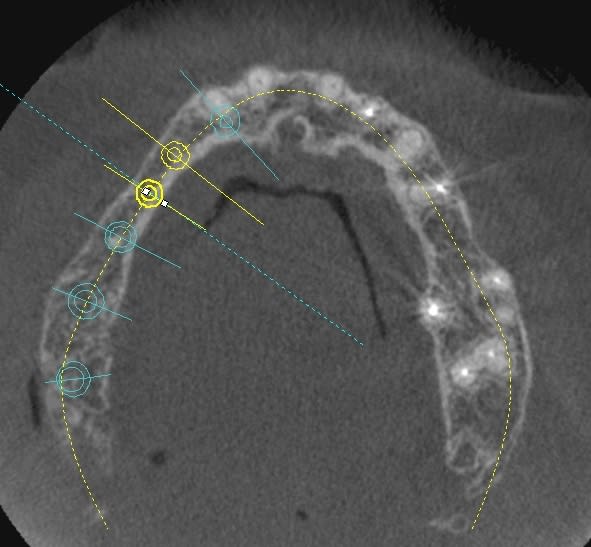

une petite étude de ton cas avec implants osseosped Astra :

12 : 3.5 x 11

13 : 3 x 11 (?)

14 : 3 x 11 (?)

15 : 3.5 x 11 (?)

16 : 4 x 11

17 : 4 x 11

je ne pratique pas donc pas de conseils sur ces implants.

techniquement:

extraction de 12 , curetage soigneux.

vue la qualité osseuse :

si D4 :

saignée à la lame n°15

si D3 :

avec un disque diamanté 10 x 0.3mm incision crestale de 12 à 16 ou 17

puis avec un disque de 20x0.3mm ou à la lame 15 approfondissement de la saignée

puis expansion en "douceur" (sans incision de décharge verticale, à priori car la ligne de crête est relativement droite)

pose de tes implants et dans ce cas, le VitalOs me semble idéal.

la difficulté majeure sera la corticale palatine qui ne semble pas géniale et qui méritera une attention particulière, ostéotome de Tatum +++

honnêtement je ne commencerais pas par un cas comme celui ci sans une solide connaissance de la sensibilité osseuse.

pas de provisoire